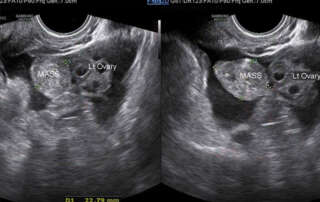

Funneling of the urethra in Valsalva (Article 1) and a phrenic (Diaphragm) endometriosis